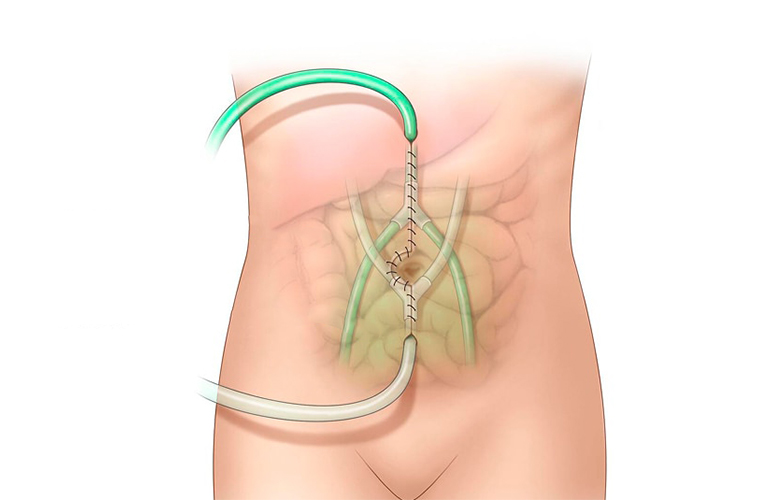

Detaylı BilgiHIPEC

HIPEC olarak adlandırılan karın içi sıcak kemoterapi uygulaması, hem hastanın yaşam süresinin uzatılması hem de hayat kalitesinin yükseltilmesi yönünden bu alanda atılan en önemli adımlardan biridir.